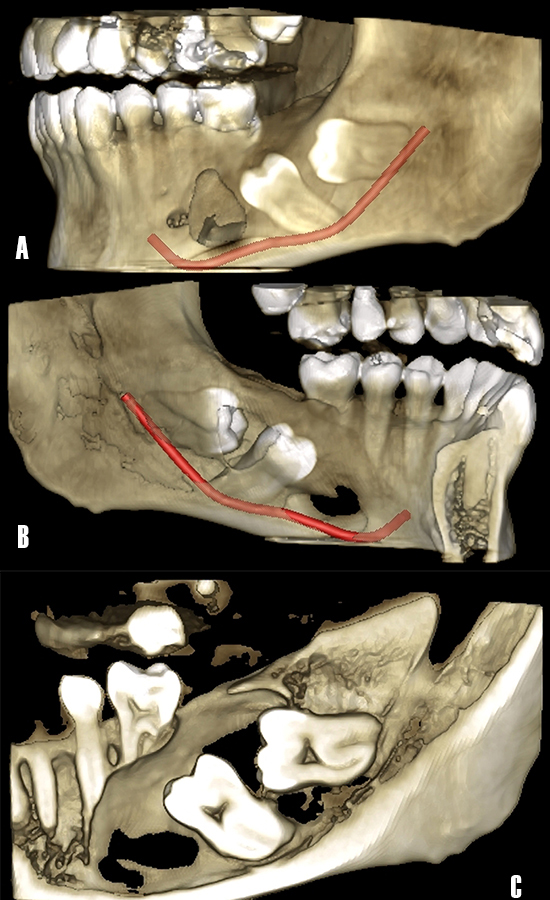

En la reconstrucción tridimensional a partir de la TCHC, se pudo observar con mayor claridad la afectación de las corticales vestibular (Fig. 4A) y lingual (Fig. 4B), además se observó la rizólisis de las raíces de los dientes 3.6 y 3.5 (Fig. 4C).

Figura 4. Reconstrucción tridimensional a partir de TCHC. A) Vista de la afectación de la cortical vestibular en el tercer cuadrante, nótese la proximidad del nervio dentario inferior. B) Vista de la afectación de la cortical lingual. C) La extensión antero posterior de la lesión osteolítica ha producido la rizólisis de las raíces del primer molar y segundo premolar.